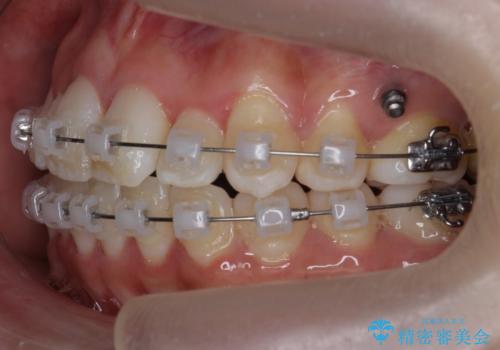

前歯は重度のがたつき、また奥歯はすれ違っていました。

治療は3年以上かかりそうと説明しましたが、2年台で終わらせることができました。

上下左右4本抜歯の可能性を説明していましたが、実際は上顎2本の小臼歯抜歯で済みました。

矯正用インプラントを使用して治療しています。